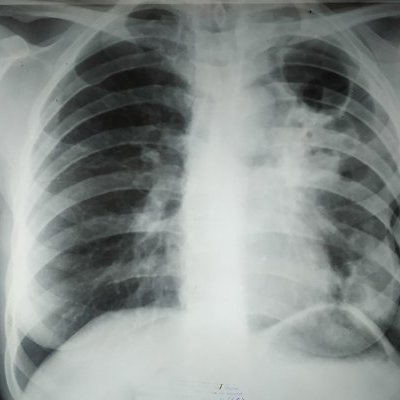

Ученые достигли значительного прорыва в диагностике туберкулеза (ТБ), предлагая потенциальное решение для преодоления вызовов, стоящих перед текущими методами диагностики.

С учетом того, что ТБ уносит жизни 1,5 миллионов человек ежегодно, раннее выявление является ключевым в борьбе с этим смертельным инфекционным заболеванием. Существующие диагностические инструменты медленны, дороги и недоступны, особенно в регионах с низким уровнем доходов, где туберкулез более распространен.